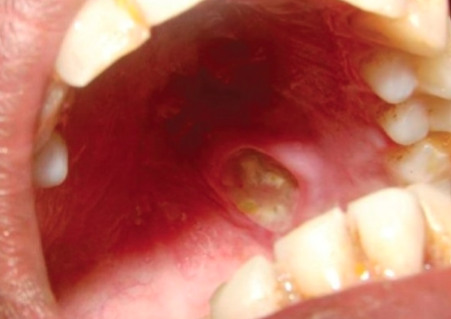

necrotizing sialometaplasia

uncommon lesion locally destructive inflammatory condition of salivary gland

ischemia leading to infarction of glands

hard palate

mimics malignancy

what is the clinical appearance of necrotizing sialometaplasia?

begins as painful, non-ulcerated swelling and develops over 2-3 weeks with necrotic tissue sloughing and a non-painful ulcer

necrotizing sialometaplasia image